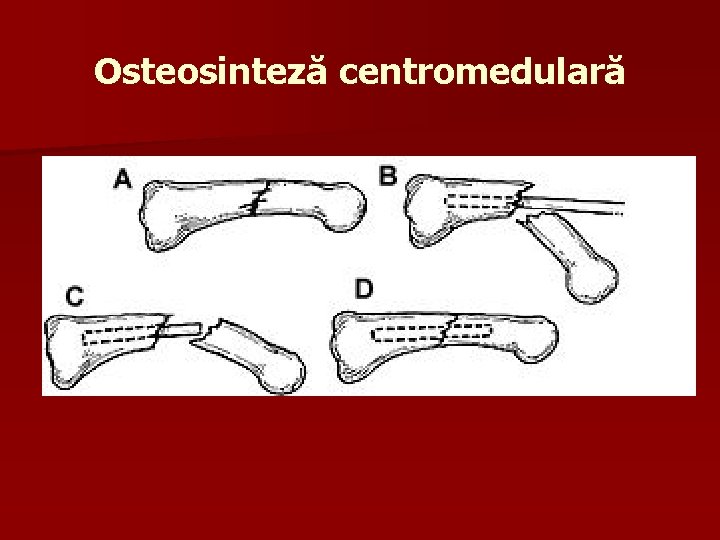

Osteosinteză centromedulară